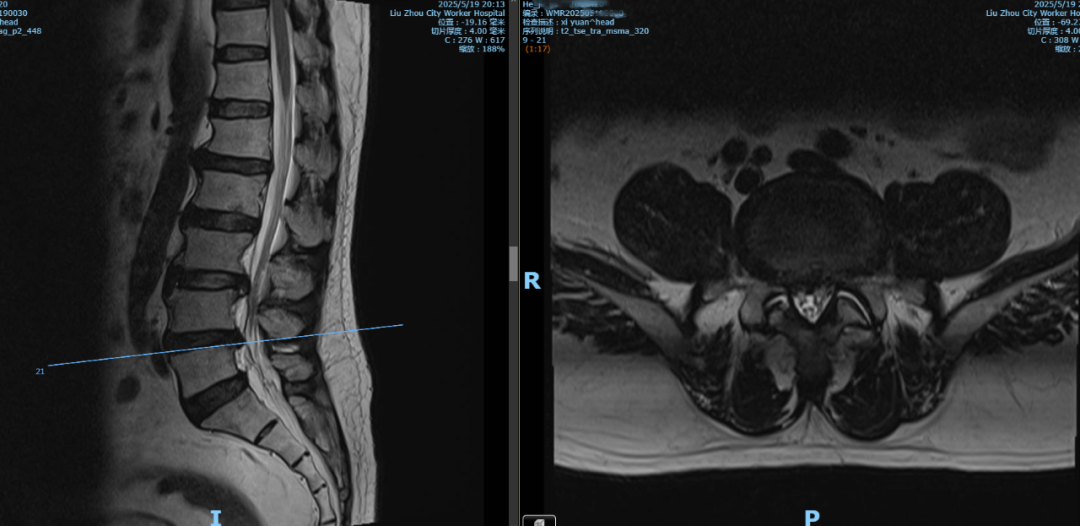

何先生今年65岁,患有脑梗、冠心病、高血压病等多种基础病,特别是腰腿痛多年,两个月前腰痛伴左下肢疼痛剧烈,弯腰时症状明显,到外院就诊被诊断为“L3/4、L4/5腰椎间盘突出”。

由于何先生患有多种基础病,病情复杂,手术风险巨大,辗转多家医院,均未能解决问题。经朋友介绍,近日,何先生在家属陪伴下来到柳州市工人医院西院(柳州市骨科医院)脊柱外科就诊。脊柱外科主任彭小忠接诊后,诊断患者有腰椎间盘突出、腰椎失稳、冠状动脉粥样硬化、高血压、脂肪肝、脑梗死,双眼白内障、青光眼,头颅、颈椎椎动脉狭窄还放置有血管支架。

患者术前影像资料显示,L3/4、L4/5腰椎间盘突出并腰椎不稳